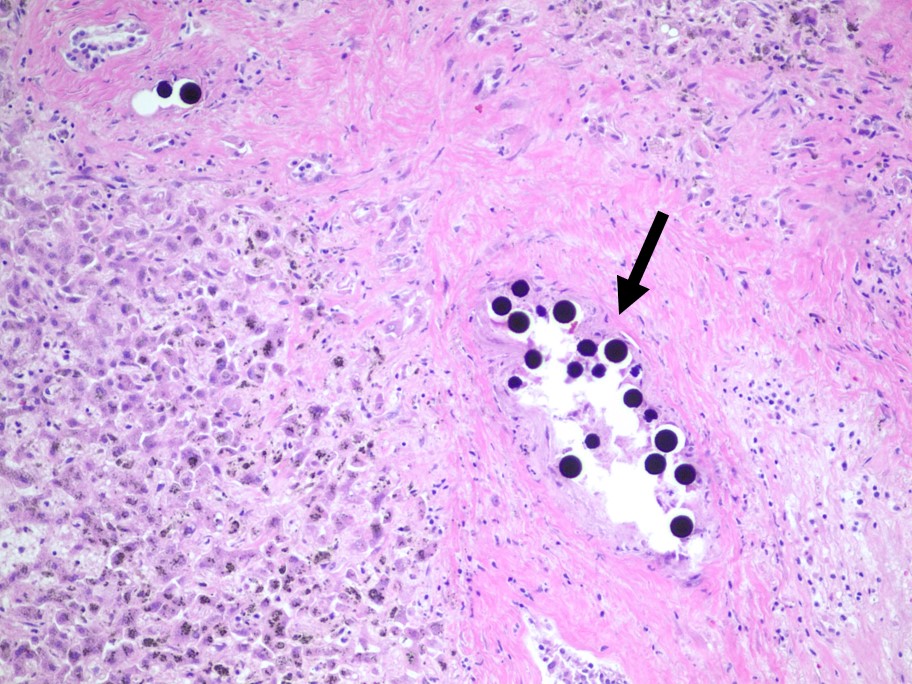

A teaching point from our Editors. How do you distinguish between intrapancreatic bile duct carcinoma and pancreatic ductal carcinoma? Samuel Freire